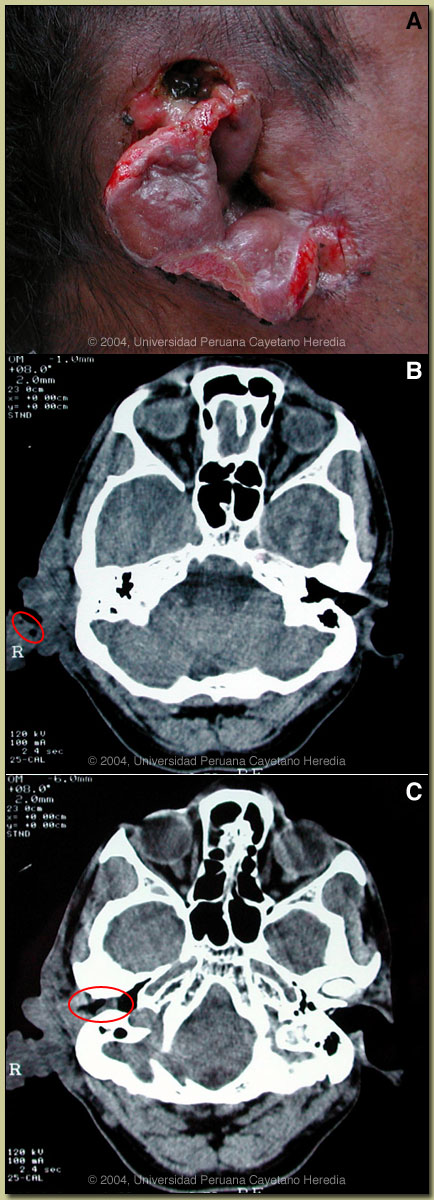

History: 49 yo male with 3-month history of non-healing wound over the right retro-auricular area after an injury caused by an adobe brick. Slow progression of necrosis to the ear itself with liquid and purulent discharge from multiple sinus tracts. No fever, no headache, no neurological symptoms. Only local care received. History of periodic convulsions since age of 8 with no previous care or workup. Last seizure 2 days prior to admission. Patient is a heavy drinker.

Epidemiology: Farmer; born and lives in the Cuzco area in the Andean highlands. No history of TB or HIV risk behavior. Physical Examination: Afebrile. Normal vital signs. Normal CNS examination. Wound is shown in image A. Laboratory Examination: Hematocrit 32%, WBC 8400, 68% polys, 8% eos; AST 32, ALT 31. Chest x-ray normal. CT scan of the head shows a soft-tissue mass of the skin and soft tissue in the right auricular area corresponding to the physical examination with several areas of subcutaneous emphysema [see image B]. There is a collection in the right external ear canal [see image C].

Discussion: After removing most of the necrotic tissue, approximately 20 live maggots were removed [see image D]. On further questioning the patient related that similar larvae had been discharged from the wound on several occasions beginning perhaps a month after the initial trauma. In reviewing the CT [see red circle, image B], the subcutaneous emphysema likely represents larval tracks in the tissue. The maggots are fourth stage Cochliomyia hominivorax [see image E]. The distinctive features of Cochliomyia are: smooth external aspect (opposite to hairy maggots), pigmented (other species are unpigmented) dorsal tracheal trunks, and two features difficult to observe in the present image; open peritreme (at the tail) and posterior spiracles not in cavity.